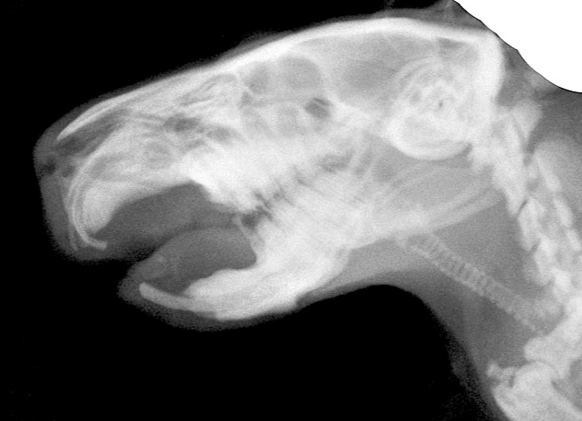

隅角虹彩角領域(隅角付近)の石灰化は骨性分離腫と呼ばれ、分離腫の骨化には骨細胞が存在しますので、単純な組織の石灰化は無細胞です。したがって、この病態は骨性分離腫と呼ばれて、石灰化の一種ではありません。